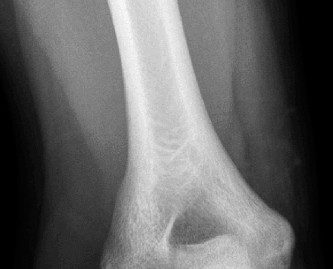

Treat a patient with infected total shoulder arthroplasty? CASE 21 A 70-year-old, right-hand-dominant female presents to clinic complaining of 4 years of gradually worsening chronic right shoulder pain and stiffness. She says the pain is worse at night and with any range of motion, denies a history of trauma, pain in other extremities, or numbness or tingling of the right upper extremity. She notes that her mother suffered from rheumatoid arthritis that affected her shoulder. Physical examination reveals decreased muscle bulk over the right supra- and infraspinatus fossae compared to the contralateral side, limited active and passive ROM, marked weakness with external rotation, and 4+/5 strength with shoulder abduction. X-rays of the right shoulder are shown in Figures 2–58 and 2–59.

The correct answer is (C). Rotator cuff tear arthropathy consists of a combination of rotator cuff insufficiency, glenohumeral joint degenerative changes, and superior humeral head migration. It is more common in women and also more often found on the dominant side. The patient’s clinical examination with weakened external

rotation and muscle atrophy signaling incompetent supra- and infraspinatus muscles point to rotator cuff insufficiency, and her plain films reveal narrowed glenohumeral joint space as well as superior migration of the humeral head. Choice D is incorrect because, while radiographs would show narrowing of the glenohumeral joint space, they would also likely show numerous osteophytes and posterior wear of the glenoid. Choice B is incorrect because, while adhesive capsulitis does present as decreased active and passive range of motion, the patient’s constellation of symptoms pointing towards rotator cuff insufficiency along with the radiographs make cuff tear arthropathy the more likely choice. Finally, Choice A is incorrect because even though she has a positive family history of rheumatoid arthritis, it is less likely to present only in a single joint. Also, rheumatoid arthritis on radiography appears more as an erosive process without the characteristic superior migration of the humeral head.

The correct answer is (A). Superior migration of the humeral head would be most indicative of chronic rotator cuff insufficiency associated with cuff tear arthropathy, as it is a direct result of the inability of the rotator cuff tendons to help maintain the humerus in its normal position. Acetabularization of the undersurface of the acromion is commonly associated with superior migration of the humeral head found in rotator cuff tear arthropathy, and can be assessed using the Hamada classification, which is based on measurements of the acromiohumeral interval on radiography (Table 2–8). Choices B and C are incorrect because, while narrowed glenohumeral joint space and subchondral sclerosis are associated with rotator cuff arthropathy on radiographs, they indicate degenerative joint changes rather than chronic rotator cuff insufficiency. Choice D is incorrect because it is not a specific sign of rotator cuff arthropathy.